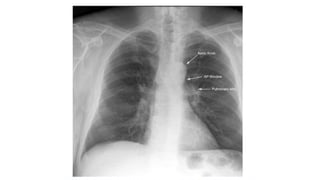

Mediastinum

• The trachea should be centrally located or slightly to the right

• The aortic arch is the first convexity on the left side of the

• The pulmonary artery is the next convexity on the left, and the

branches should be traceable as it fans out through the lungs

• The lateral margin of the superior vena cava lies above the right heart

border

Mediastinum • The tracheashould be centrally located or slightly to the right • The aortic arch is the first convexity on the left side of the mediastinum • The pulmonary artery is the next convexity on the left, and the branches should be traceable as it fans out through the lungs • The lateral margin of the superior vena cava lies above the right heart border